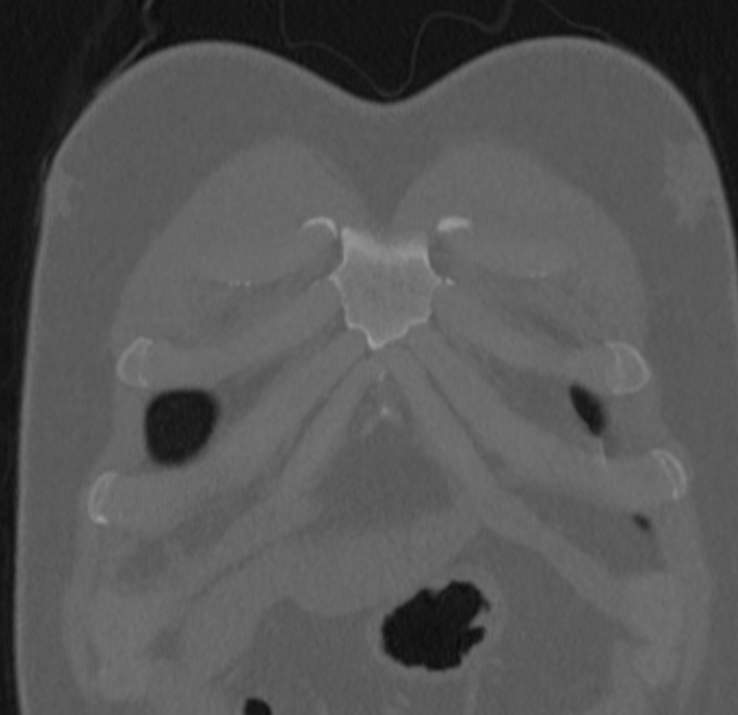

Грудина представляет собой удлиненную плоскую кость, напоминающую по своей форме кинжал и расположенную вертикально в середине груди. К ней с обеих сторон при помощи хрящей крепятся ключицы и ребра, образуя грудную клетку. Грудина выполняет защитную функцию для сердца и крупных сосудов, а также участвует в процессе кроветворения, благодаря расположенному в ней красному костному мозгу.

При проведении мультиспиральной компьютерной томографии на снимках и трехмерных изображениях хорошо видны костные структуры грудины, передней поверхности ребер, грудино-ключичных и грудино-реберных сочленений. Также можно увидеть строение и патологические процессы в органах средостения: трахеи, пищевода, лимфатических узлов средостения, вилочковой железы, загрудинно расположенной щитовидной железы, грудной аорты, сердца и перикарда, жировой клетчатки средостения.

С помощью мультиспиральной КТ грудины можно диагностировать: